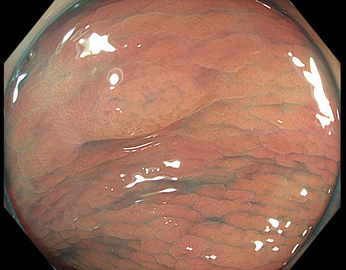

TXIは、「画像の構造を強調する」技術です。これは特別に目新しいものではありません。パソコンの画像編集ソフトや、スマホのアプリでも御馴染みの技術です。しかし、「どのような構造強調が実際に、内視鏡に一番、合うか?(強すぎると不自然になる!)」は、難しい(アナログ的な)課題です。オリンパス社は数タイプのTXIモードを用意しました。半年間の試行錯誤の末、今では下記のモードがベストと判断しました。そして今では「TXI無しの内視鏡は不要(フルタイムTXI)」というまで常用しています。

以下に実例を挙げます

写真だけ、見ると「言われてみるとTXIの方が認識しやすい。でも僅かの差」と感じるでしょうが、この「僅かの差」が、人間の脳での検出には大きな差になります。青い色素(インジゴ・カルミン)が非常に強調され、粘膜の凸凹が明瞭になるのが特徴です。

通常観察 TXIモード